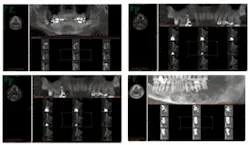

Three-D imaging creates virtual, rotating models that illustrate in 360 degrees the complete nature and makeup of the human jaw and face. It gives dentists greater accuracy, precision, and efficiency.

The complete 3-D scan of the face is then displayed on a computer screen, making it possible for all dentists and dental specialists to analyze the complete surface. The scan also exposes issues previously undetectable with traditional methods.

These features provide dentists with a patient’s complete mouth, face, and jaw anatomy and allow us to clearly see all underlying dental structures, soft tissue, bone, and nerve canal details. This can lead to discovering the unexpected well in advance of a procedure.

For example, the i-CAT in our office produces distortion-free images, making it compatible with other vendors’ software programs. Applications such as Simplant and Nobel Guide help us plan major reconstructive surgeries. We also have stereolithic models constructed from our i-CAT to assist in major deformity and trauma reconstruction.